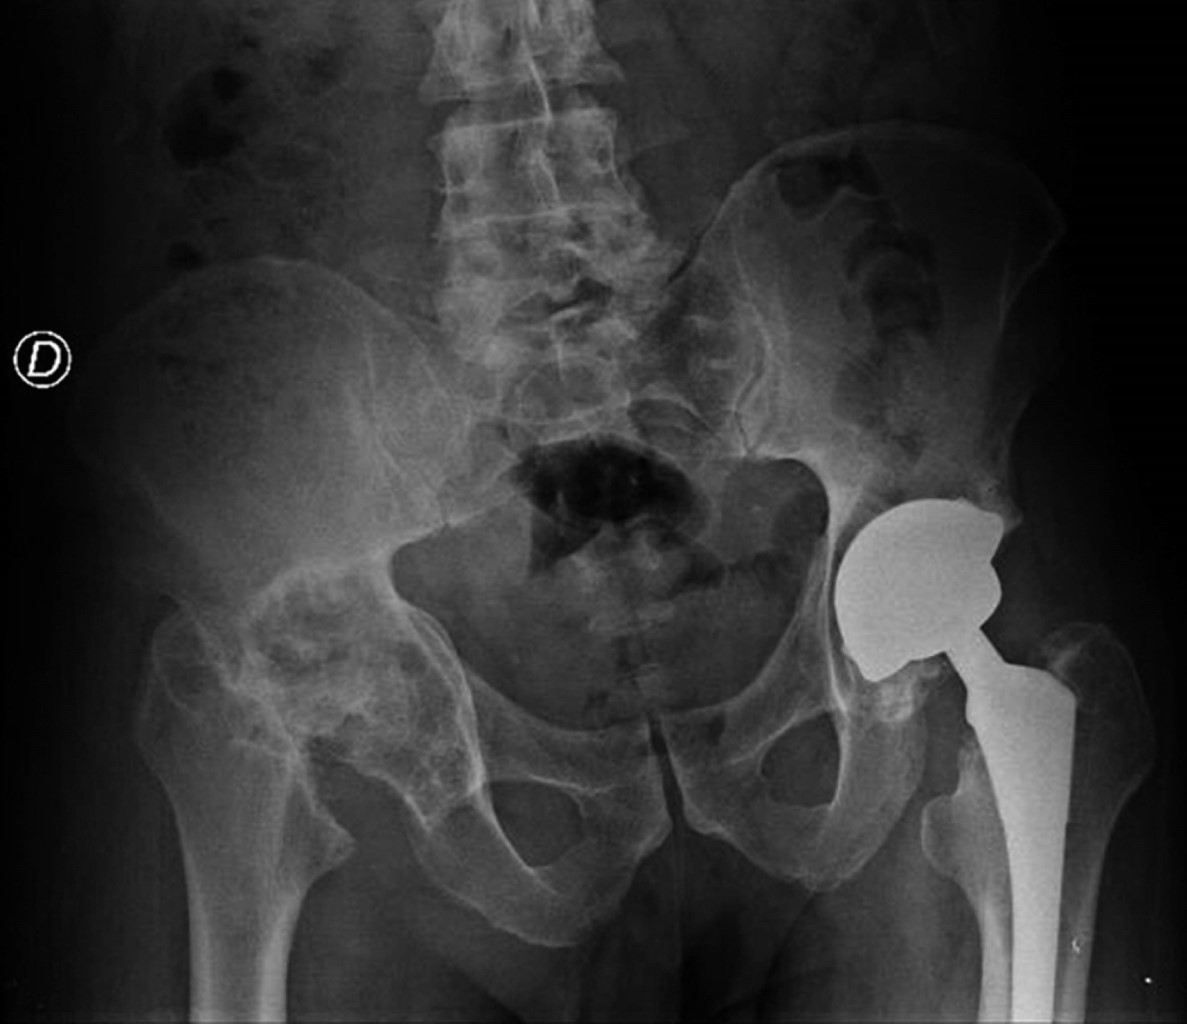

Se realiza radiografía anteroposterior (AP) de pelvis donde se observa pérdida de la esfericidad de la cabeza femoral, presencia de osteofitos, esclerosis con colapso subcondral, disminución del espacio articular, todo compatible con cambios degenerativos avanzados que se acompañan de cambios acetabulares secundarios a la osteonecrosis. En la cadera izquierda se observan componentes protésicos acetabular y femoral adecuadamente colocados y orientados, sin datos de interfaz, lisis o aflojamiento (Figura 1). Para identificar adecuadamente la morfología femoral y acetabular, se toma tomografía computarizada donde se aprecian múltiples quistes subcondrales, así como defecto óseo contenido, con pérdida considerable de hueso esponjoso principalmente de la pared posterior (Figura 2).

Figura 1